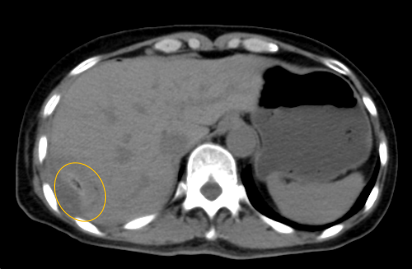

入院后,影像診療中心立即給李女士完善了CT和MR檢查,發(fā)現(xiàn)病變位于肝包膜下,臨近膈肌,消融治療過(guò)程中有并發(fā)損傷膈肌的可能,難度較大,但是采用精準(zhǔn)影像定位是可以完成的。陳寶瑩主任立即與腫瘤三病區(qū)劉金鵬主任聯(lián)系,并與影像微創(chuàng)治療小組進(jìn)行MDT討論:患者為卵巢癌肝右葉包膜下單發(fā)轉(zhuǎn)移瘤,最長(zhǎng)徑不超過(guò)3cm,患者對(duì)局部治療的主觀愿望強(qiáng)烈,符合消融治療專(zhuān)家共識(shí),遂制定了影像引導(dǎo)下局部消融治療聯(lián)合全身治療的綜合治療方案。

針對(duì)這個(gè)特殊部位的腫瘤,要想消融完全,那么膈肌損傷的風(fēng)險(xiǎn)就很高,陳寶瑩主任帶領(lǐng)影像微創(chuàng)亞專(zhuān)業(yè)組成員仔細(xì)閱讀CT圖像,設(shè)計(jì)進(jìn)針路徑,結(jié)合MR圖像確定腫瘤活性范圍,制定了周密而詳盡的消融計(jì)劃。臘月二十九,即住院第二天影像微創(chuàng)治療小組圓滿(mǎn)為患者完成了腫瘤微波消融治療,觀察24小時(shí)后出院回家過(guò)年。術(shù)后48小時(shí)隨訪(fǎng)患者無(wú)明顯不適,術(shù)后7天隨訪(fǎng),患者肝功、血常規(guī)等各項(xiàng)指標(biāo)均恢復(fù)正常。